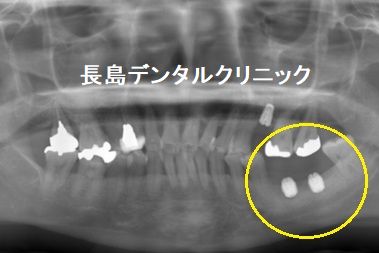

いいますと、抜歯後骨の再生を待つことにしました。抜歯すると失わ

れた骨は再生します。ただ100%再生しません。炎症の度合い、骨の

吸収の度合いにより骨の再生量様々ですが、ある一定期間骨の再生を

待ってから、無事安全にインプラントを埋入することができました。

2、インプラント埋入